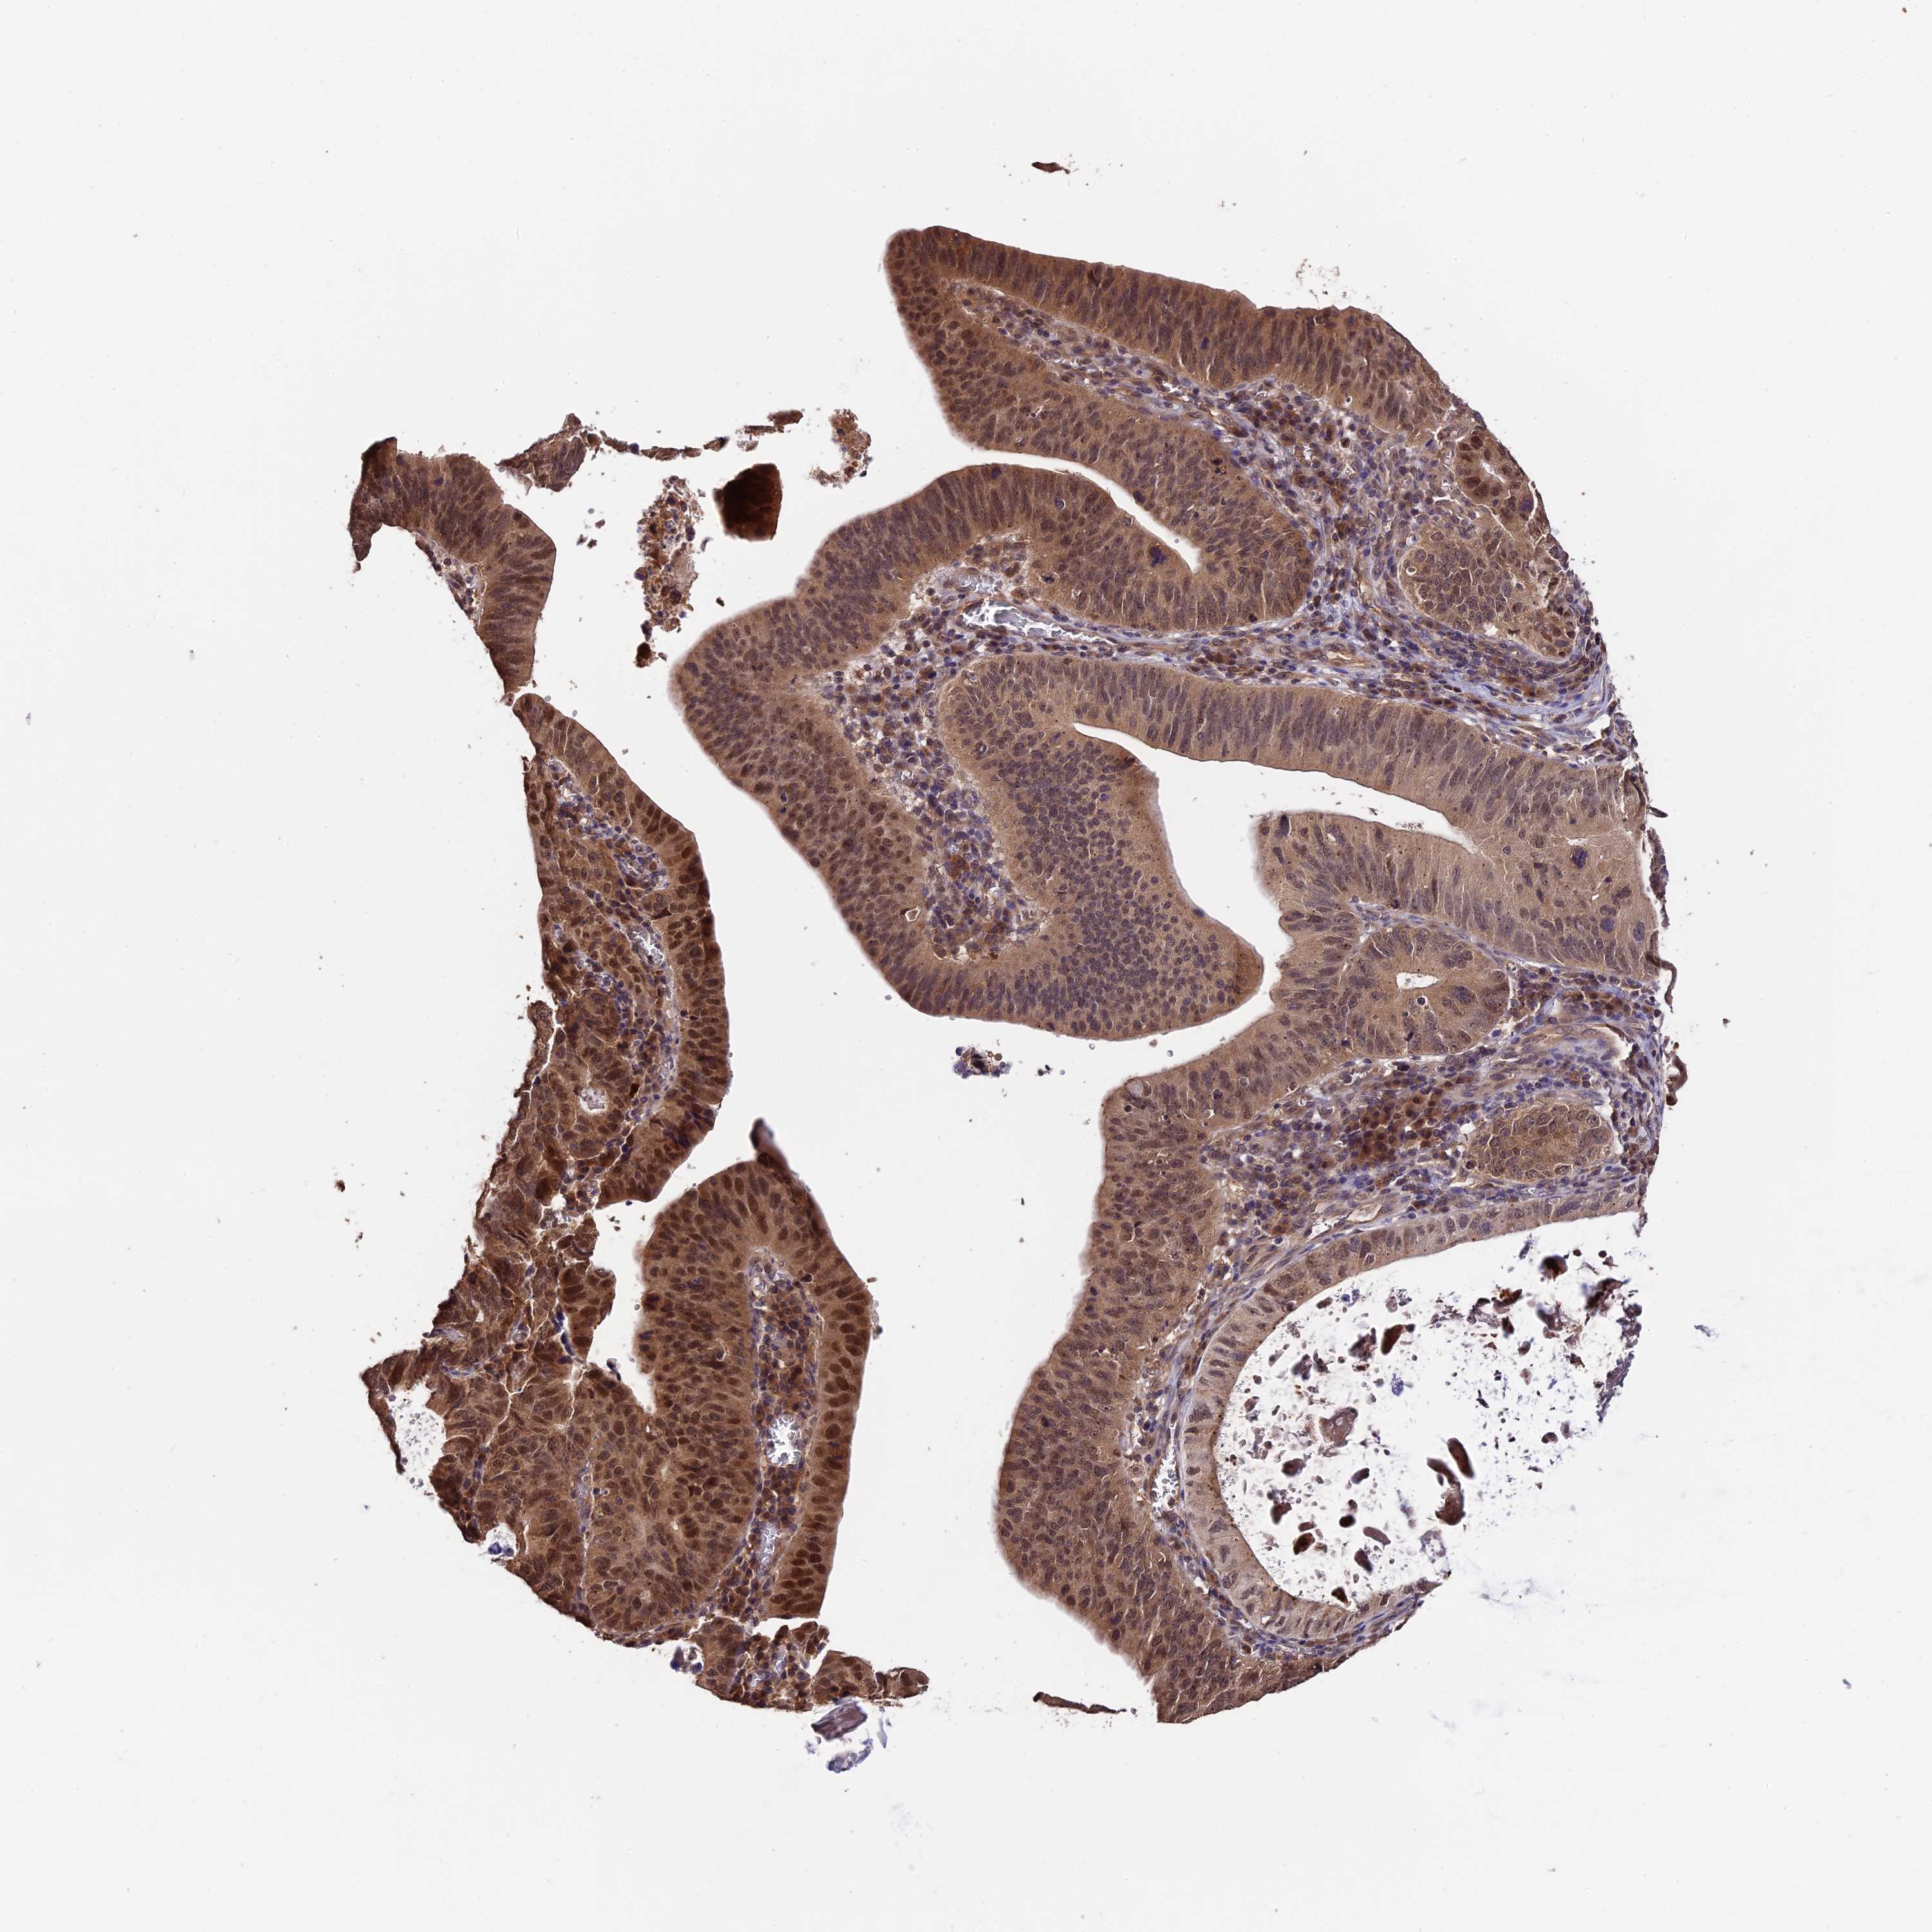

STOMACH CANCER - Protein expressioni

A mouse-over function shows sample information and annotation data. Click on an image to view it in a full screen mode. Samples can be filtered based on level of antibody staining by selecting one or several of the following categories: high, medium, low and not detected. The assay and annotation is described here.

Note that samples used for immunohistochemistry by the Human Protein Atlas do not correspond to samples in the TCGA dataset.

Antibody stainingi

Antibody staining in the annotated cell types in the current human tissue is reported as not detected, low, medium, or high, based on conventional immunohistochemistry profiling in selected tissues. This score is based on the combination of the staining intensity and fraction of stained cells.

Each image is clickable and will lead to virtual microscopy that enables deeper exploration of all samples and also displays staining intensity scores, fraction scores and subcellular localization as well as patient and tissue information for each sample.

Antibody HPA041130

Antibody HPA041380

Staining

High

Medium

Low

Not detected

Intensity

Strong

Moderate

Weak

Negative

Quantity

>75%

75%-25%

<25%

None

Location

Nuclear

Cytoplasmic/membranous

Cytoplasmic/membranous,nuclear

Adenocarcinoma, NOS